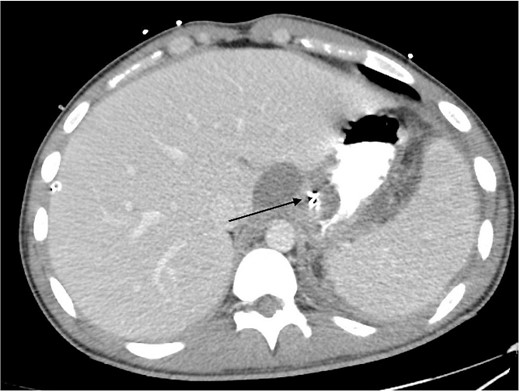

A 21 year old male presented to the emergency department with 1 day of abdominal pain and vomiting. Seven days earlier, a laparoscopic Nissen fundoplication, posterior cardiopexy, and anterior gastropexy for reflux aspiration were performed. Medical history included a left branchial cyst and asthma. Gastroscopy 3 years prior demonstrated reflux oesophagitis and small hiatus hernia, with no previous surgeries. On examination, blood pressure was 118/85 mmHg, with tachypnoea to 40 breaths per minute and tachycardia to 121 beats per minute. He was peritonitic. Laboratory results demonstrated C-reactive proteinof 543 mg/dL and Lactate of 5.9 mmol/L. He was commenced on intravenous fluid resuscitation and piperacillin-tazobactam. Computed tomography (CT) abdomen demonstrated large amounts of intra-abdominal free fluid, and more than expected pneumoperitoneum for laparoscopy performed 7 days prior, as seen in Fig. 1. Nasogastric tube (NGT) and indwelling urinary catheter were inserted, and the patient was organized for a damage control diagnostic laparoscopy +/− laparotomy.

Non-contrast CT abdomen/pelvis in axial view demonstrating diffuse intra-abdominal free fluid with multiple large locules of intraperitoneal free air.